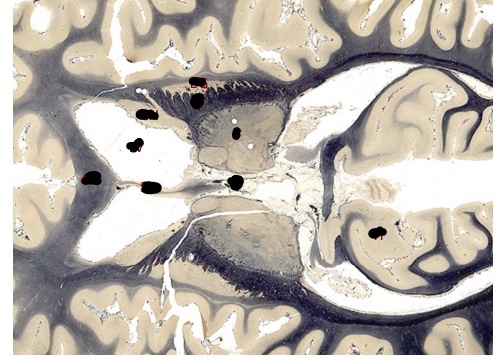

caudal coronal cut

label, note important features